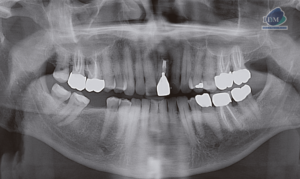

Paciente femenina de 51 años acude al Instituto para realizarse una tomografía volumétrica para rehabilitación oral, a la evaluación de la radiografía panorámica se observa

Paciente femenino de 69 años acude al Instituto para realizar una tomografía con fines de rehabilitación oral, a la evaluación de la radiografía panorámica se